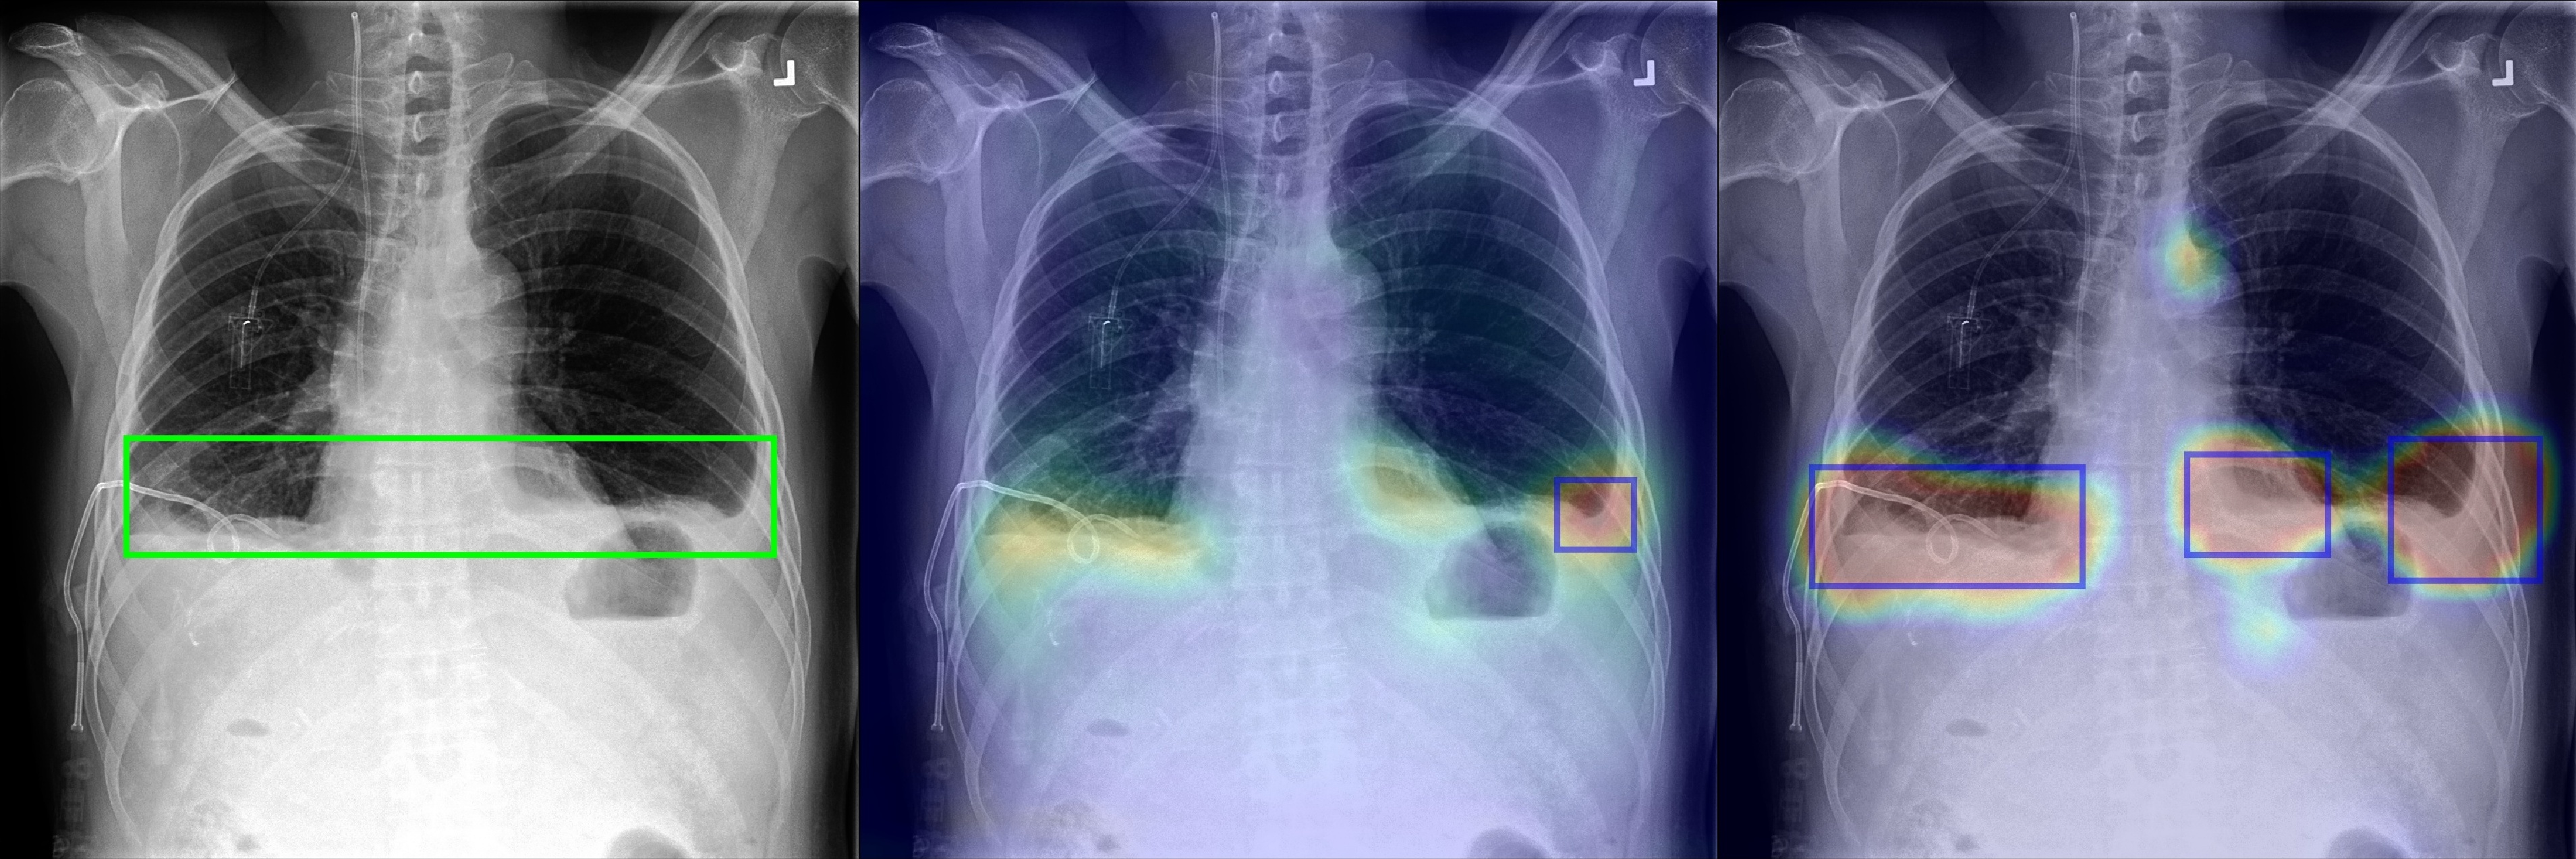

Figure 2 shows a few selected examples of the probability maps generated by PCAM pooling and the class activation maps generated by LSE pooling together with the predicted bounding boxes. Compared to the class activation maps, the probability maps are visually more clear with sharp boundaries around lesion regions. We attribute the improved visual quality to the probabilistic interpretation of the sigmoid-bounded class activation map and explicitly using it for training with global pooling.

We notice the probability maps generated by PCAM pooling tend to enlarge regions of interest in general than class activation maps from LSE pooling, especially when the ground truth regions are small, such as “Nodule” in Figure 2. This may explain the fact that PCAM pooling has relatively larger average false positives than CAM with LSE pooling.

Figure 2: Selected samples of localization heatmaps and their bounding boxes generated by LSE pooling and PCAM pooling on the test set of ChestX-ray14 [7]. In each subfigure, the left panel is the original chest X-ray with the ground truth bounding boxes (green), the middle panel is the class activation map and predicted bounding boxes (blue) by LSE pooling, the right panel is the probability map and predicted bounding boxes (blue) by PCAM pooling.